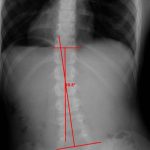

Отличить и понять, что перед нами сколиоз 2 степени (фото 2), можно потому, что его признаки внешне видны. Сколиоз 2 степени, бывает значительно труднее определить, если человек имеет лишнюю массу тела. До 8 лет часто обнаруживают сколиоз первой степени, который исправляется с помощью массажа.

Если после 18 лет образовался сколиоз второй степени, то это не так опасно. Все потому, что шансы на дальнейшее прогрессирование минимальные. Сколиоз спины (фото 2.1) также определяют современным методом, с помощью специального теста Ресслера. Способ помогает исключить риск перехода в последующую степень, потому как s-образный сколиоз 2 степени нередко становится причиной защемления нерва.

В большинстве случаях, s-образный сколиоз 3 степени (фото 3) бывает комбинированного типа. Это значит, что искривлению подвергается и поясничный и грудной отдел. Приобретенный сколиоз 40 градусов искривления, уже относят к этой степени. Сколиоз 3 степени сопровождается следующими признаками: